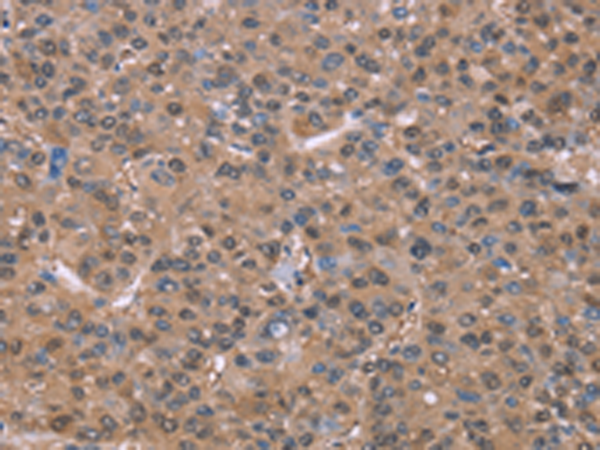

分类: 科研抗体货号: P04914别名: H963应用: WB,IHC反应种属: Human